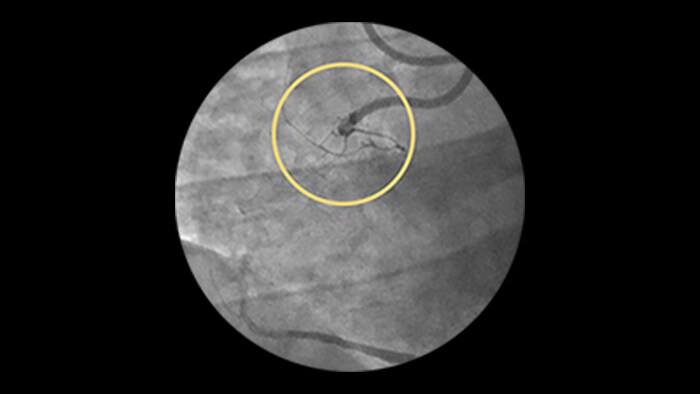

LAD In-Stent Restenosis: iFR and IVUS Co-registration, laser atherectomy, final DCB and stenting